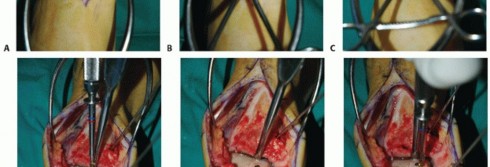

- TECH FIG 3 • A. The dimensions of the recipient site are carefully recorded and transferred to the allograft. B. Two pointed reduction clamps are used to stabilize the allograft during preparation. C. Donor allograft with newly prepared graft removed.

Carefully mark the dimensions for graft harvest on the allograft (TECH FIG 3A).

Same location on the allograft talus as the recipient site on the native talus

If you err, err to have the graft slightly too large. Be sure to account for saw blade thickness. “Measure twice and cut once.”

You have only one opportunity, so be sure the measurements and orientation of the saw blade for each cut are optimal.

The allograft can be stabilized with two large pointed reduction clamps (TECH FIG 3B).

Extract the graft from the donor talus (TECH FIG 3C).

Reduce the immunogenic load from the graft by washing the graft's cancellous surfaces with saline. - Implanting and Securing the Graft into the Recipient Site

It is unlikely that a perfect clinical and fluoroscopic match will be achieved. Attempt to achieve the best clinical match of the graft's articular surface with the surrounding native cartilage (TECH FIG 4A).

If the clinical match is appropriate, then the fluoroscopic match is not important.

We routinely secure the graft with one or two small-diameter solid screws (1.5 or 2.0 mm in diameter). One is typically placed from dorsal to plantar and the other from medial to lateral (if the depth of the graft will allow) (TECH FIG 4B,C).

Place the screws in lag fashion.

Countersink the screw heads below the articular surface (TECH FIG 4D,E).

Using fluoroscopy, confirm that the graft and hardware are in optimal position (TECH FIG 4F-H).

The graft will not look perfect fluoroscopically, but as long as the clinical appearance is acceptable, the outcome has a good chance to be favorable.

The hardware may appear slightly proud fluoroscopically despite being countersunk. The talar dome is not a flat plane, and therefore the screw may seem to be protruding. Moreover, the articular cartilage is rather thick compared to such a low-profile screw head.

- TECH FIG 4 • A-C. Fitting and securing the graft to the native talus. A. After contouring the graft (some minor discoloration from debris while manipulating graft on back table; it is easily washed away). B. Drill hole perpendicular to graft. C. Securing graft with two countersunk screws. (continued)